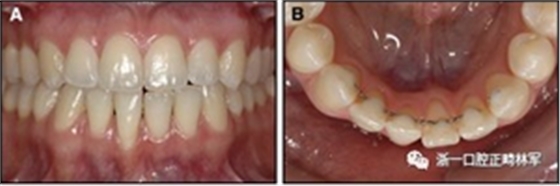

圖3.極軟弓絲完全完好,在多個(gè)空間平面上的拱形歪斜,右側(cè)尖牙的面部?jī)A斜以及右側(cè)側(cè)切牙和中切牙在相反方向上的扭矩:A,頰面視圖; B,咬合面視圖。